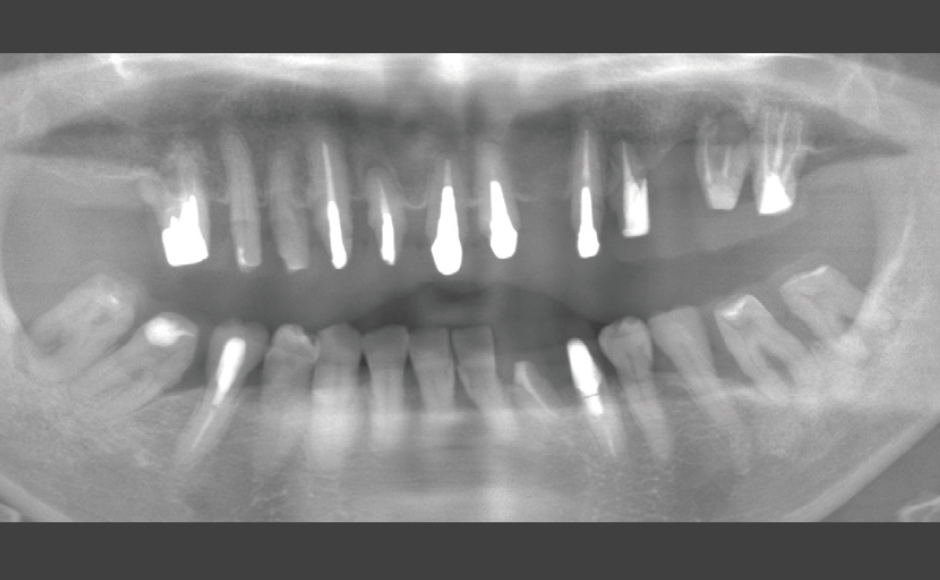

歯周病および根尖病巣により骨吸収、動揺が激しく、抜歯適応の歯牙に対し非外科的に歯周治療をNd:YAGレーザーを用いて行い、歯牙の保存を試みた症例